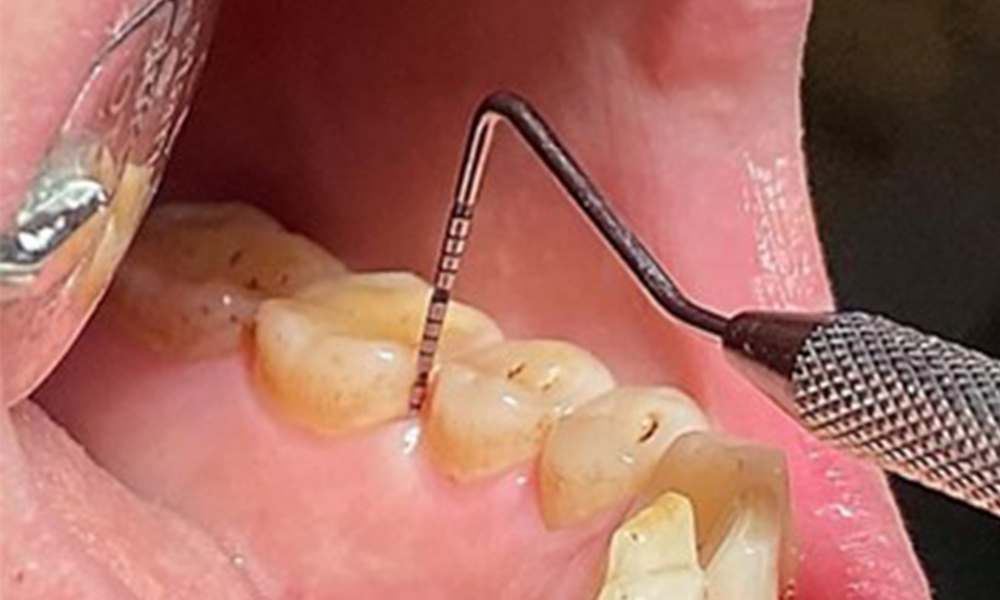

Die klinischen Sondierungstiefen liegen mit 1-3mm im physiologischen Bereich. Im Oberkiefer zeigen

sich von 13-16 sowie 23-27 Rezessionen bis 1mm. Der BOP liegt bei 15%.

Aufgrund des guten allgemeinmedizinischen Zustandes ist der aus der Mundgesundheit ermittelte Bedarf maßgebend für die Behandlung. Die regelmäßige Erhebung der Sondierungstiefen ist unabdingbar. Die gingivale Blutung ist bei Rauchern herabgesetzt, weswegen die klinische

Diagnose einer Parodontitis nur durch Sondierung möglich ist (Abb. 7). Die ausschließliche Erhebung von Blutungsindizes verdecken unter Umständen das Bild einer bestehenden Parodontitis oder Gingivitis. (5)